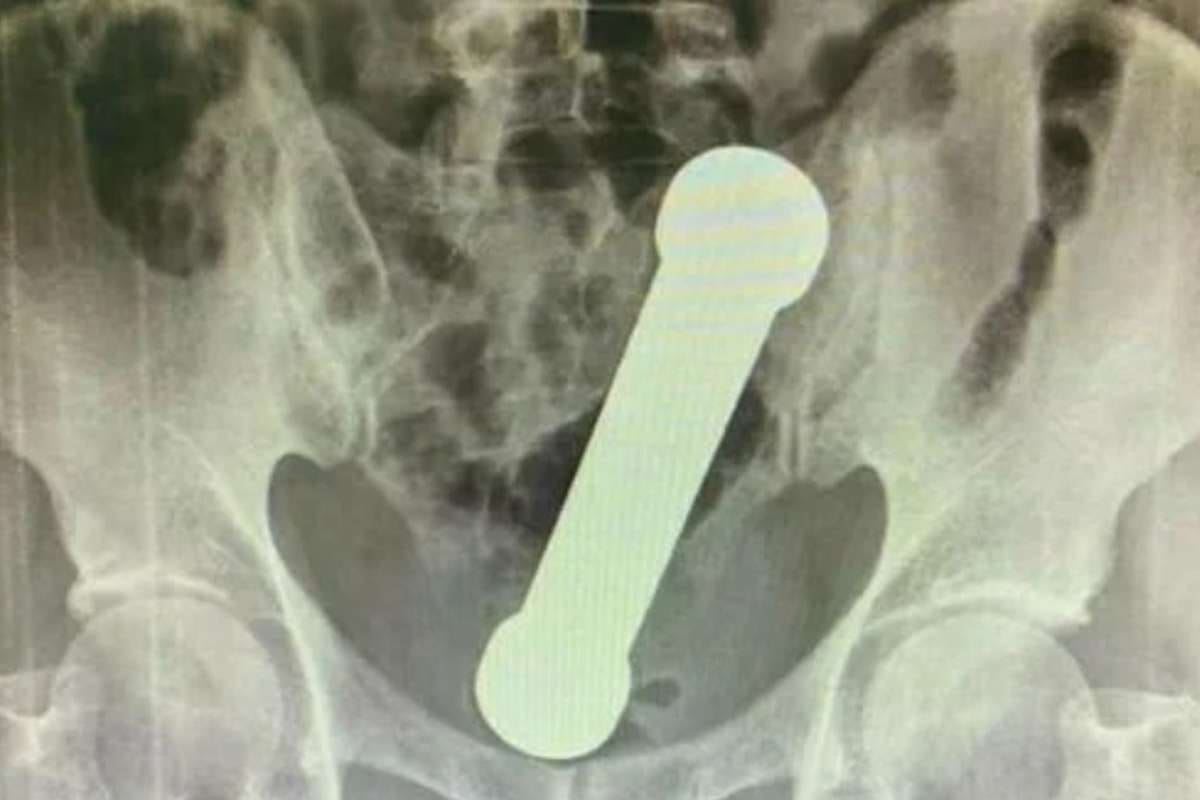

Médicos tiram peso de academia de dois quilos de reto de paciente

Homem de 54 anos procurou atendimento médico relatando dores no estômago